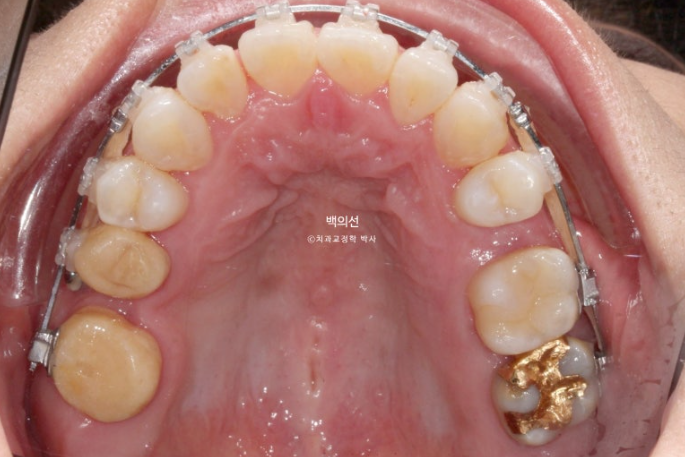

이후 발치공간 폐쇄 및 교정용 나사인 미니스크류를 이용한 거미스마일 개선 치료를 더 진행 후 25년 6월, 치료를 마무리 했습니다. 총 치료기간은 2년 6개월입니다.

25.06

교정과 크라운치료를 모두 마친 후 클리피씨 브라켓을 제거한 모습입니다.

브릿지를 잘라낸 공간은 교정으로 깔끔히 마무리 되었고 교정 중 사용한 임시치아는 교정 마무리 시점에서 흰색 크라운으로 교체되었습니다.